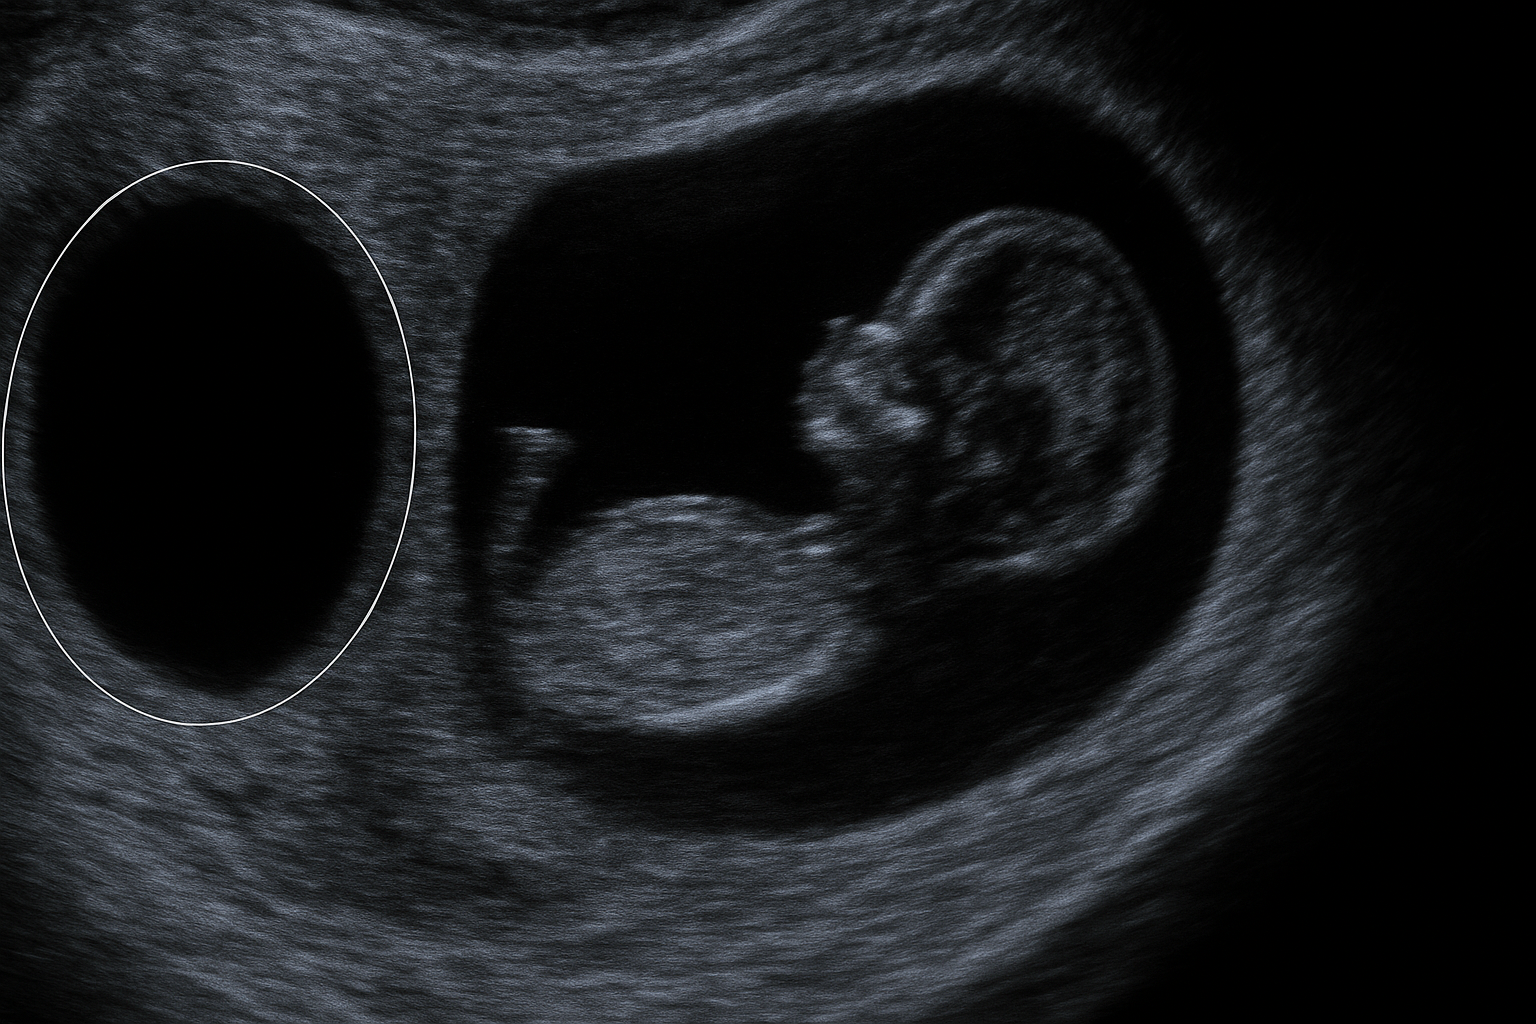

Viele Schwangerschaften beginnen als Zwillingsschwangerschaft – doch nicht immer kommen zwei Kinder zur Welt. Beim sogenannten "Vanishing Twin Syndrome" stirbt ein Zwilling bereits im Mutterleib. Das medizinische Phänomen ist gut dokumentiert – die psychologischen Folgen hingegen sind kaum erforscht.

Das "Vanishing Twin Syndrome" beschreibt den frühen Verlust eines Zwillings im Mutterleib, meist durch Resorption des Embryos. Medizinisch werde das klar eingeordnet, sagt Dr. Reinhard Haller, einer der bekanntesten Psychiater Österreichs. Doch die psychische Dimension ist bisher kaum systematisch untersucht.

Das Vanishing Twin Syndrome bezeichnet den frühen Verlust eines Zwillings im Mutterleib. Der verstorbene Embryo wird meist vom Körper der Mutter resorbiert und verschwindet "spurlos".

Schätzungen zufolge beginnen bis zu 20 % aller Schwangerschaften als Zwillingsschwangerschaften. In vielen Fällen stirbt ein Embryo frühzeitig, oft unbemerkt.